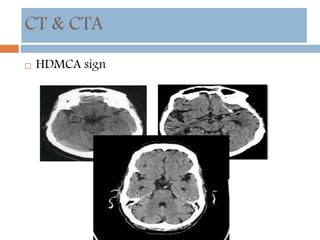

CT & CTA

 HDMCA sign

CT & CTA HDMCA sign